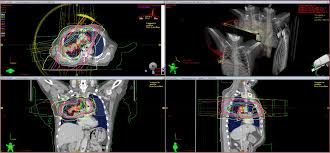

강도 조절 고정밀 방사선 치료(IMRT)는

방사선 치료 계획 장치(전용 컴퓨터)를 이용해

암의 위치나 형태에 맞추어 선량의 강도를 세밀하게 조정합니다.

컴퓨터의 도움으로 복잡한 형상의 병소에서도

선량을 정확히 집중시킬 수 있는 것입니다.

이런 고정밀도 조사에 빼놓을 수 없는 것이

이미지 유도 방사선 치료(IGRT)라는 위치 맞춤 기술입니다.

암의 병소는 치료일마다 내장의 충만도나 호흡에 따른

움직임으로 인해 미세한 위치 변화가 생길 수 있습니다.

이전에는 위치 변화를 예상해

병소 주위에 1~2cm의 여유를 갖고 넓게 방사선을 쏘았습니다.

IGRT는 치료 당일에 영상을 촬영해

치료 계획과의 오차를 보정하기 때문에

조사 여유를 5mm 정도까지 줄일 수 있습니다.